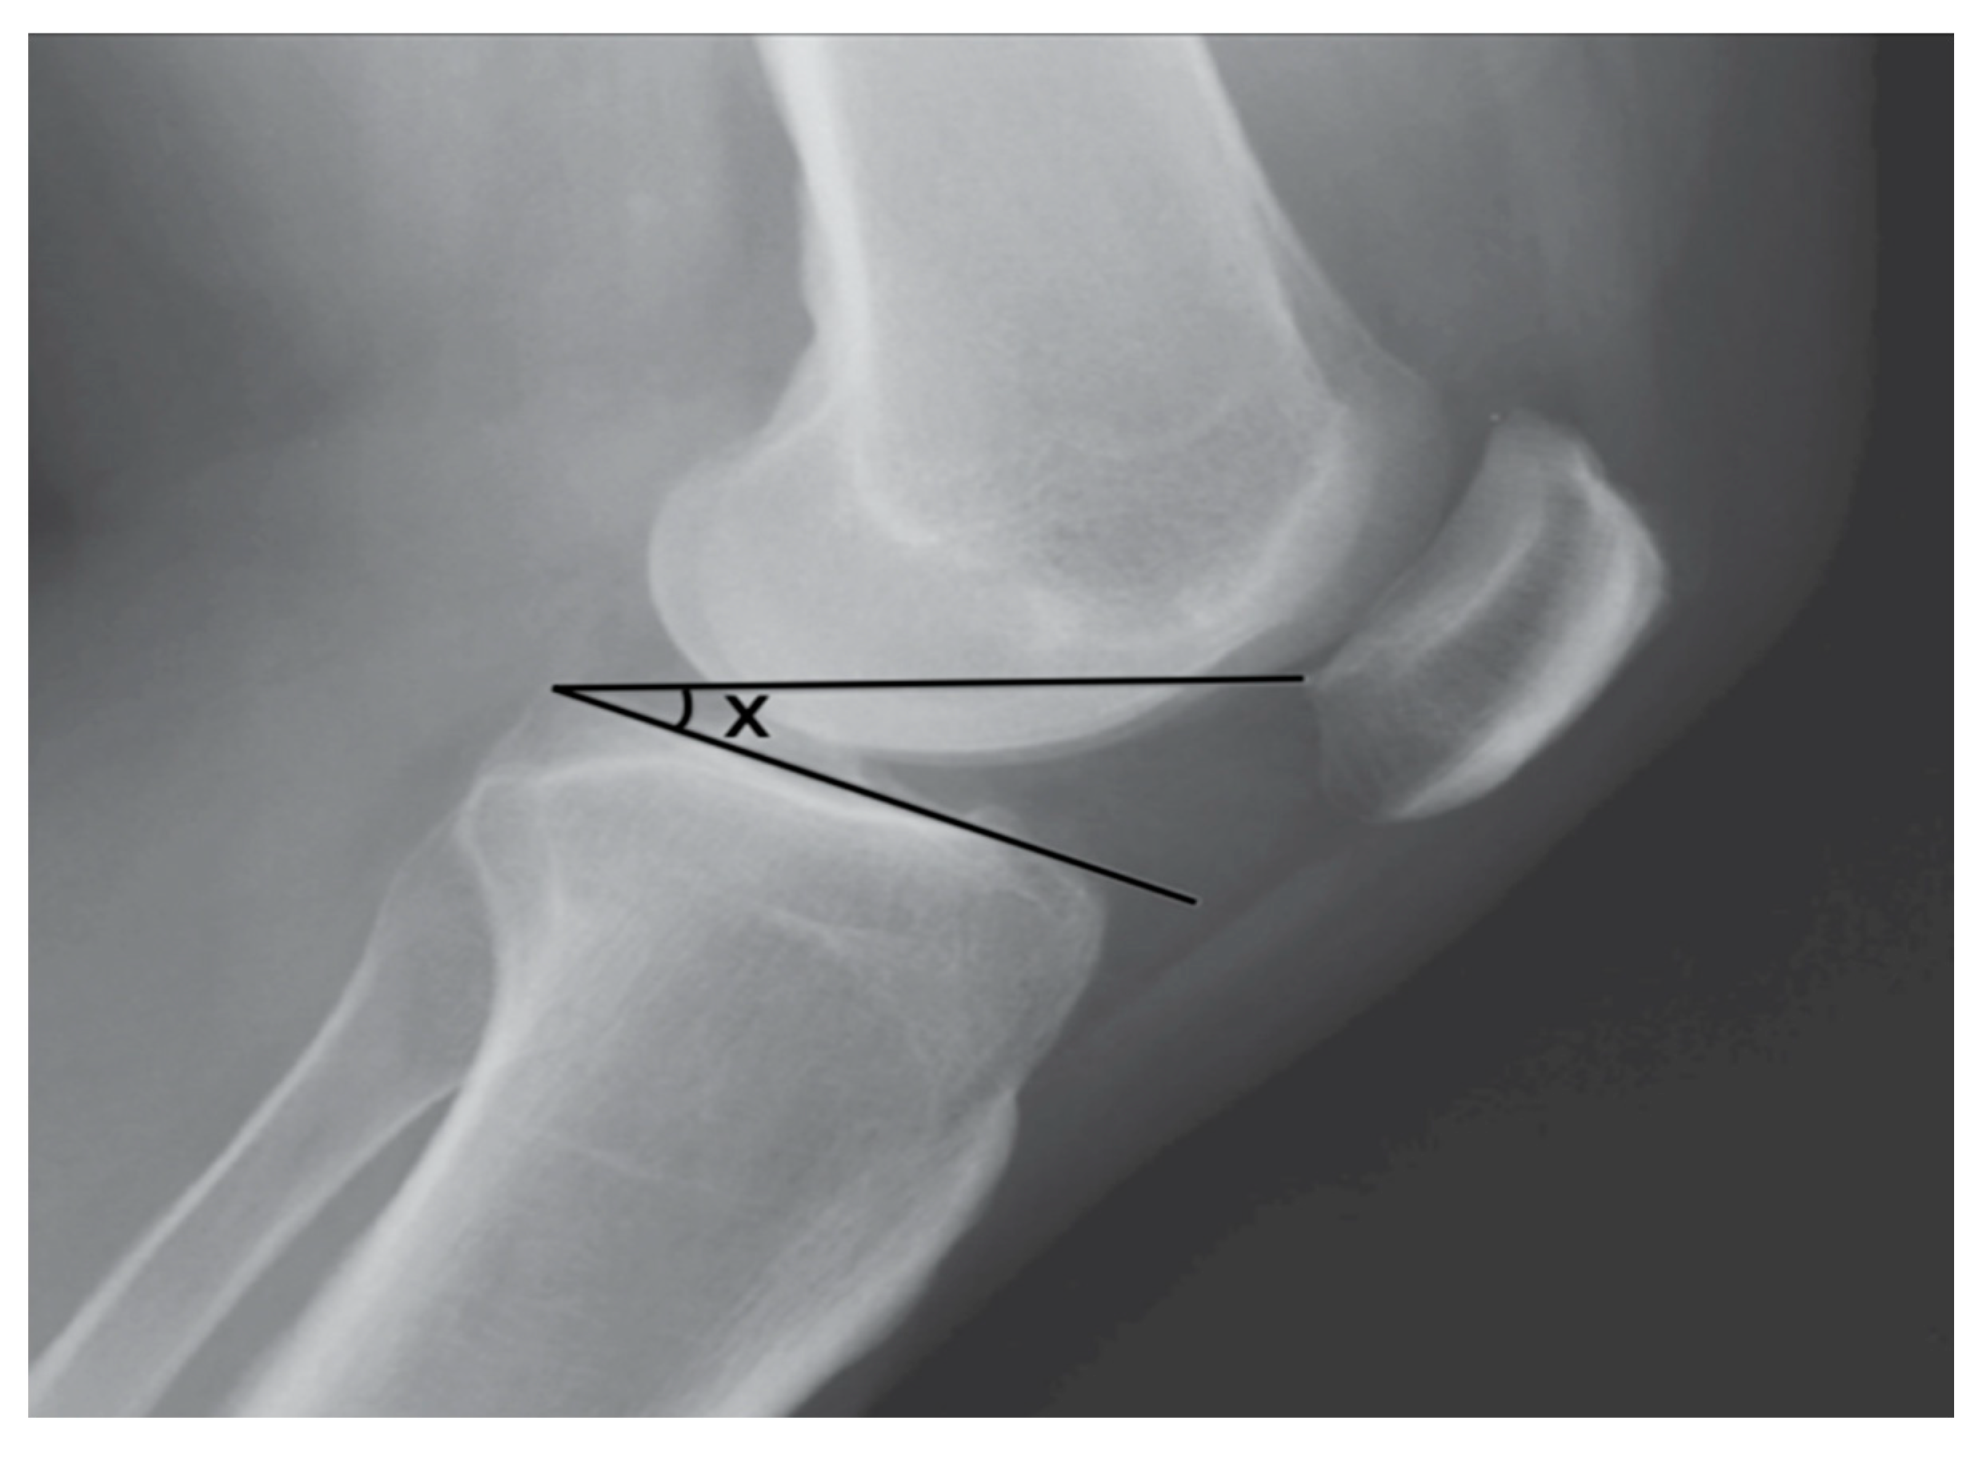

- Bonadio, M.B.; Torres, J.A.P.; Filho, V.M.; Helito, C.P. Plateau-patella angle: An option for assessing patellar height on proximal tibia osteotomy. Acta Orth. Bras. 2016, 24, 127–130. [Google Scholar] [CrossRef] [PubMed][Green Version]

- De Carvalho, A.; Andersen, A.H.; Topp, S.; Jurik, A.G. A method for assessing the height of the patella. Internat. Orthop. 1985, 9, 195–197. [Google Scholar] [CrossRef]